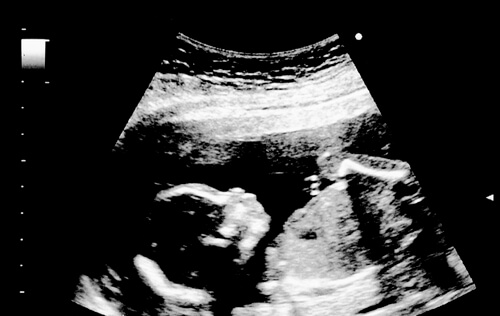

Na 18ª semana de gravidez, o bebê mede 14 centímetros ou 5,5 polegadas. Seu peso é de 190 gramas aproximadamente. Seus movimentos ficam cada vez mais fortes. Em uma ultrassonografia, será possível ver o bebê esticar e dobrar as extremidades do corpo. Assim como abrir e fechar a boca no aprendizado de engolir.

É possível ver os vasos sanguíneos devido à transparência da pele. Os cílios e as sobrancelhas começam a aparecer. E as orelhas e os olhos assumem a posição de uma fisionomia normal. Em uma ultrassonografia, é possível observar o bebê colocar os dedos na boca.

Bocejar ou fazer caretas. Alguns bebês podem, até mesmo, ter soluços durante a ultrassonografia. Através desses exames, também é possível ver o bebê pular no seu cubículo natural.